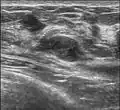

Since both fibroadenomas and breast lumps as a sign of breast cancer can appear similar, it is recommended to perform ultrasound analyses and possibly tissue sampling with subsequent histopathologic analysis in order to make a proper diagnosis. Unlike typical lumps from breast cancer, fibroadenomas are easy to move, with clearly defined edges.[1][2]

A fibroadenoma is usually diagnosed through clinical examination, ultrasound or mammography, and often a biopsy sample of the lump.[8] Suspicious findings on imaging may result in a person needing a biopsy in order to gain a definitive diagnosis. There are three types of biopsies: fine-needle aspiration, core-needle biopsy and surgical biopsy. The method of biopsy depends on the appearance, size and location of the breast mass.[18]